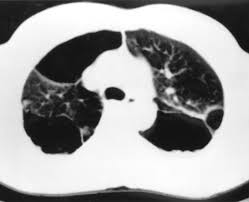

Bullous lung disease symptoms. There are several subtypes of emphysema including subcutaneous emphysema bullous. Group B GOLD 1 or 2. Most people with bullous emphysema experience shortness of breath wheezing coughing up phlegm and centralized pain in their chests especially when engaging in physical activity.

This emphysema also includes deterioration of alveolar tissue and this is basically lung tissue that makes up the walls between air sacs. Bullous Lung Disease is the most common form of emphysema. As the disease gets worse scars form and the tissue becomes stiff and thick.

Emphysematous bullae can cause many respiratory problems including shortness of breath. Your FEV 1 is between 50 and 80. The harmful effects of tobacco smoking especially with regard to the aetiology of chronic obstructive pulmonary disease are well documented3 Large emphysematous bullae may develop usually in the context of significant tobacco exposure over many years and tend to be associated with airway obstruction reduced gas transfer factor and diffusion coefficient and evidence of centrilobular.

This is condition which is characterized by abnormal and enlarged air spaces within the lungs.